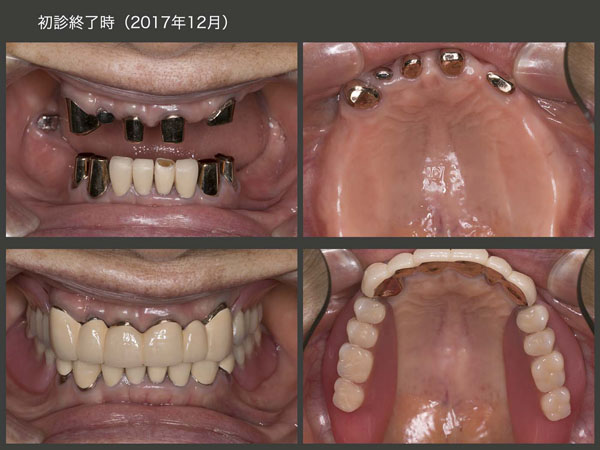

治療途中に骨折等で通院できず,治療期間は延びてしまったが,2017年12月に上下顎にコーヌス義歯を装着した.再植した右上2は動揺があるため側方力をかけないように根面板を装着するに留めた.左上3は若干の動揺があるため,少し丈の短い内冠を装着した.右上1は通常の長さの内冠を装着した.なお,3本の再植歯の歯周ポケットは3mm以下に落ち着いた.

2017年12月,初診終了時のデンタルX線写真およびパノラマX線写真.再植歯の歯根は短いが,歯根膜による歯槽骨の再生がみられた.あとは種々の力に対して抵抗できるか否かであるが,コーヌス冠による2次固定効果により残存歯を束ねたことで,何とか持ちこたえてもらいたい.